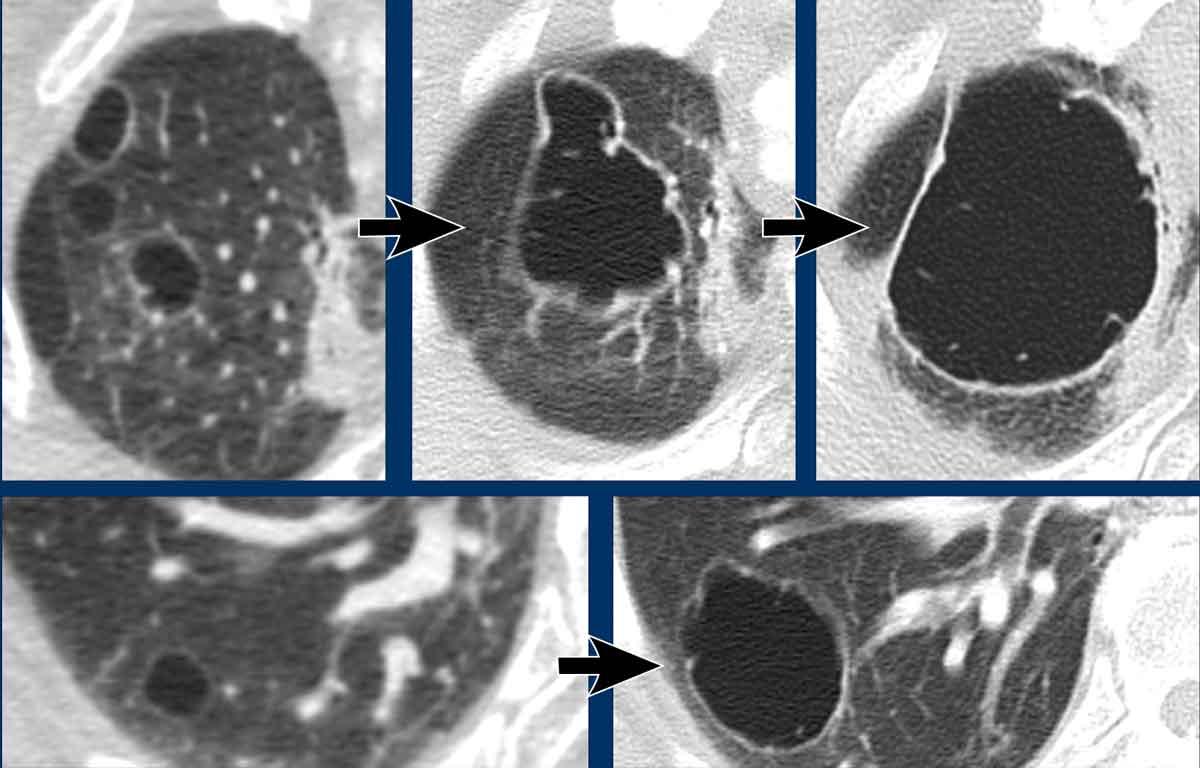

Các nang trong BHD có xu hướng phân bố ưu thế ở vùng phổi thấp và ngoại vi.

Đôi khi các nang có ranh giới được xác định bởi các vách liên tiểu thùy, tạo cho chúng hình dạng tam giác hoặc thấu kính đặc trưng (đầu mũi tên trong hình 2 và 4).

Các nang BHD không nhiều, thường ít hơn 50 nang. Đôi khi số lượng nang rất ít với hình ảnh rất tinh tế (hình 3), nhưng không được bỏ sót.

Hình ảnh

- Các nang BHD. Một số nang tiếp giáp với màng phổi (mũi tên vàng) hoặc các rãnh liên thùy. Các nang ở vùng phổi thấp cũng có thể gặp trong LIP. Khí phế thũng cạnh vách liên tiểu thùy có phân bố ưu thế ở vùng phổi trên.

- Phân bố ưu thế ở vùng phổi thấp và các nang hình tam giác (đầu mũi tên) trong BHD.

- Lưu ý hình ảnh rất tinh tế với phân bố ưu thế ở vùng phổi thấp.

- Các nang BHD điển hình

Đây là hình ảnh của một phụ nữ 56 tuổi, có tiền sử tràn khí màng phổi tái phát và hiện tại nhập viện lần này cũng vì tràn khí màng phổi (mũi tên).

Hãy phân tích hình ảnh.

Đây là các nang thực sự hay các tổn thương giả nang?

Đây là phát hiện tình cờ hay bạn cho rằng đây là bệnh phổi dạng nang?

Chẩn đoán có khả năng nhất là gì?

Nhận xét hình ảnh

Có nhiều nang thành mỏng – hơn bốn nang. Lưu ý vị trí phân bố gần các rãnh liên thùy và ở ngoại vi phổi.

Kết luận

Đây là trường hợp hội chứng Birt-Hogg-Dubé (BHD).

Bàn luận

Hai bệnh phổi dạng nang thường biểu hiện bằng tràn khí màng phổi là LAM và BHD.

LAM biểu hiện là các nang đơn thuần, thành mỏng, hình tròn hoặc bầu dục, đều đặn với phân bố lan tỏa.

Vị trí ngoại vi và cạnh rãnh liên thùy của các nang BHD thường tạo ra các góc nhọn, khiến chúng có hình dạng thấu kính.

Khi các nang có hình ảnh đặc trưng này, chúng có độ đặc hiệu cực kỳ cao cho chẩn đoán hội chứng Birt-Hogg-Dubé.

Đây là một trường hợp khác của hội chứng Birt-Hogg-Dubé.

Các nang có vị trí điển hình ở ngoại vi phổi gần trung thất (mũi tên đen) và gần rãnh liên thùy (mũi tên trắng).

Đây là một trường hợp minh họa khác với rất ít nang nhỏ ở bệnh nhân mắc hội chứng Birt-Hogg-Dubé.

Đôi khi cần phải quan sát rất kỹ các trường phổi để không bỏ sót các nang và bỏ lỡ chẩn đoán BHD.

Trong trường hợp này, có thể hình dung rằng nếu CT được thực hiện vì lý do khác, người đọc có thể dễ dàng bỏ sót những nang nhỏ này.

Cần nhớ rằng khi phát hiện hơn bốn nang và chúng thực sự là nang, cần phải xử lý các phát hiện này.

Những bệnh nhân này nên được chuyển đến bác sĩ chuyên khoa hô hấp để đánh giá thêm.

Bệnh nhân này được chụp CT để đánh giá khối u thận.

Trong báo cáo chẩn đoán hình ảnh, các nang trong phổi được mô tả là bóng khí (bullae).

Tuy nhiên, các nang này là nang BHD điển hình ở ngoại vi phổi, trong khi bóng khí thường gặp ở bệnh nhân khí phế thũng và có vị trí ở các trường phổi trên.

Đặc biệt khi chỉ thấy một vài nang, hãy nghĩ đến BHD.

Gia đình bệnh nhân cần được tầm soát hội chứng BHD và khối u thận.

Cuối cùng là một trường hợp BHD nặng hơn với các nang kích thước lớn hơn.

Bệnh nhân này nhập viện vì tràn khí màng phổi.

Lưu ý ống dẫn lưu (mũi tên).